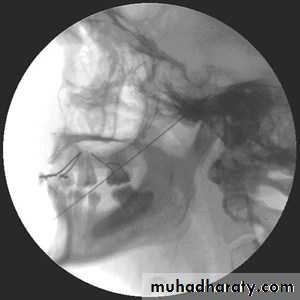

Imaging modalities used are as follows:1. Conventional radiography: it is a noninvasive, inexpensive modality;multiple views are needed (at least 2 views: anteroposterior andlateral).2. Computed tomographic (CT) scan: it has a very important role invisualizing and locating foreign bodies, even radiolucent ones; it alsoprovides information about local anatomy, tissue reaction, and abscess formation.

3. Fluoroscopy: C-arm imaging equipment allows for real timeradiographic visualization of the foreign body.4. Magnetic resonance imaging: it is used in nonmetallic foreign bodies; it provides detailed information regarding tissue reaction.5. Ultrasonography.